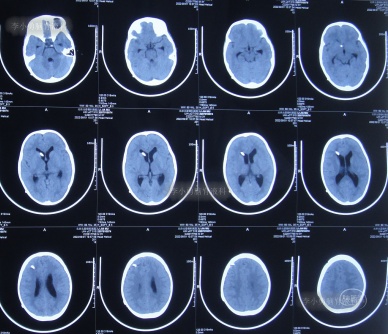

入院当天查头颅CT示脑室扩张(图-8)。

图-8:2022年7月1日入院时头颅CT